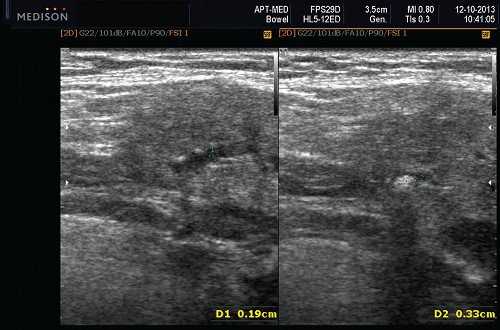

Рис. 5. Камень протока поднижнечелюстной слюнной железы.

Рис. 6. Камень в паренхиме поднижнечелюстной слюнной железы.

Рис. 7. Камень в протоке поднижнечелюстной слюнной железы.